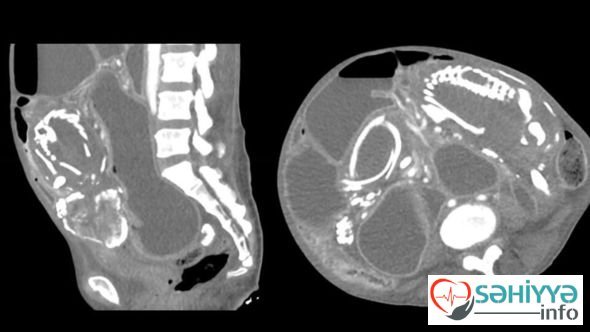

Ancaq doqquz il sonra Nyu-Yorka köçən afrikalı yenə də öz sözünü pozub və mədəsində həzm problemləri şikayəti ilə xəstəxanaya gəlib. Müayinə zamanı qadının orqanizmində həzm sisteminə təzyiq göstərən və həyati vacib qidaların orqanizmə daxil olmasına mane olan artıq daşlaşmış dölün olması müəyyən edilib.

Həkimlər xəstəyə əməliyyat olunmasını və ölən uşağı çıxartmağı təklif ediblər, lakin miqrant hər şeyin günahının Tanzaniyada ona söylənən lənətlərin olduğunu deyərək bundan imtina edib. Qadın həkimlərə öz vəziyyətini nəzarətdə saxlamağa və halı pisləşərsə, tibb işçilərinə müraciət edəcəyini vəd edib. Lakin həkimlərlə qadının növbəti “görüşü” artıq meyitxanada baş tutub. Yarılma zamanı normal qidalana bilməyən orqanizmin tükənməsi ölümün səbəbi kimi qeydə alınıb.